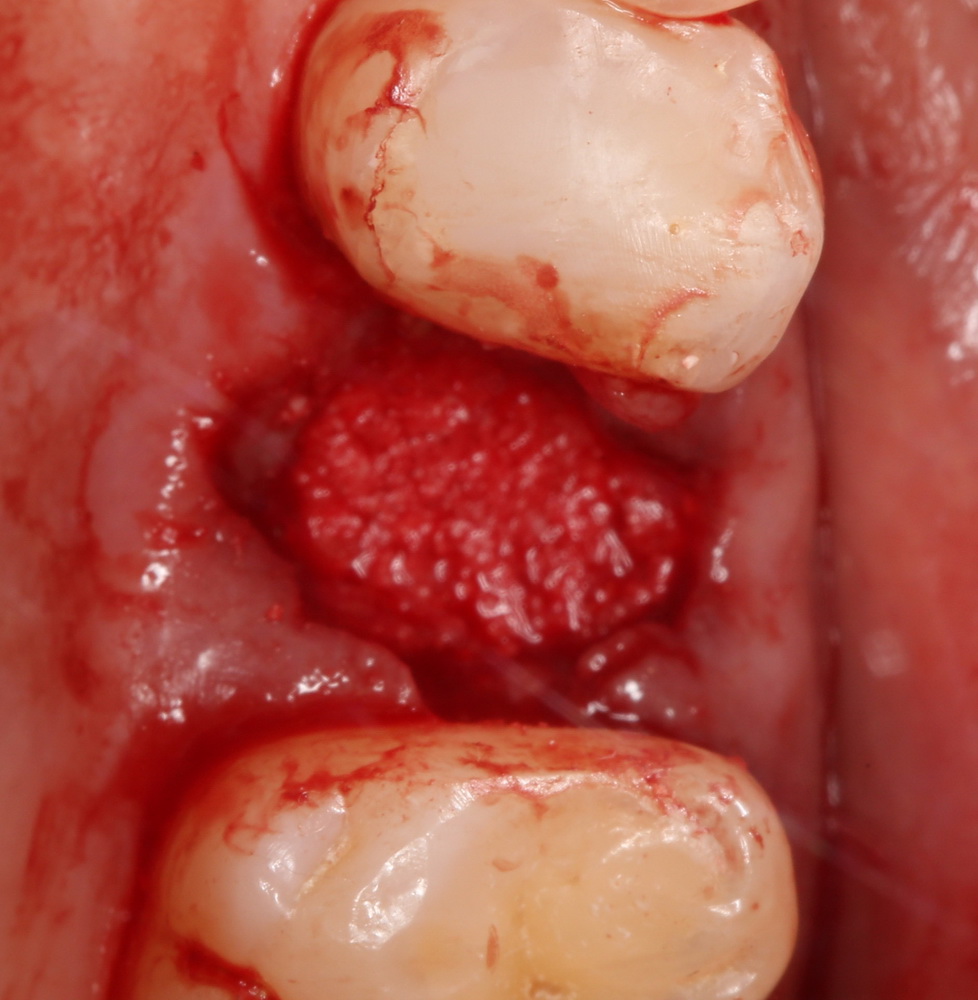

Исключение — синуслифтинг в пределах одного-двух зубов:

и превентивная аугментация лунки:

а во всех остальных случаях — обязательно!